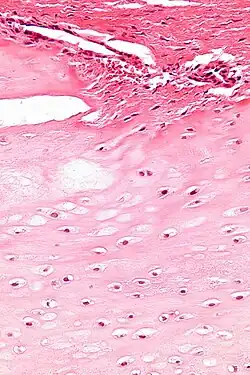

| Micrograph of an enchondroma. H&E stain. |

Enchondroma is a type of benign bone tumor that originates from cartilage. The exact etiology of it is not known. An enchondroma most often affects the cartilage that lines the inside of the bones. The bones most often involved with this benign tumor are the miniature long bones of the hands and feet. It may, however, also involve other bones such as the femur, humerus, or tibia. While it may affect an individual at any age, it is most common in adulthood. The occurrence between males and females is equal. It is not very likely that the enchondroma will grow back in the same spot; the rate is less than ten percent.